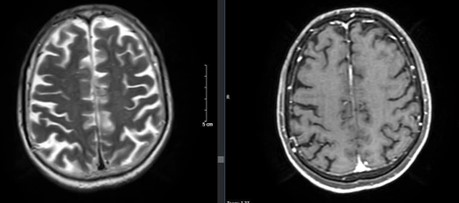

Hình ảnh chụp cắt lớp vi tính lồng ngực sau 3 chu kỳ điều trị hóa chất:

Trước điều trị

Sau điều trị

Hình 3: Hình ảnh chụp cắt lớp vi tính lồng ngực trước và sau điều trị

Nhận xét: Trước điều trị hóa chất thùy dưới phổi trái có khối tỷ trọng ngấm thuốc, thượng đòn phải và trung thất có vài hạch, nhóm 2, 4 bờ rõ, ngấm thuốc sau tiêm, các hạch dọc động mạch chủ bụng ngấm thuốc, tuyến thượng thận trái dày thân tuyến, tuy nhiên sau điều trị hóa chất 3 chu kỳ, không thấy hình ảnh khối tỷ trọng ở phổi, các hạch ở trung thất, thượng đòn, dọc động mạch chủ bụng cũng như hình ảnh dày thận tuyến thượng thận.